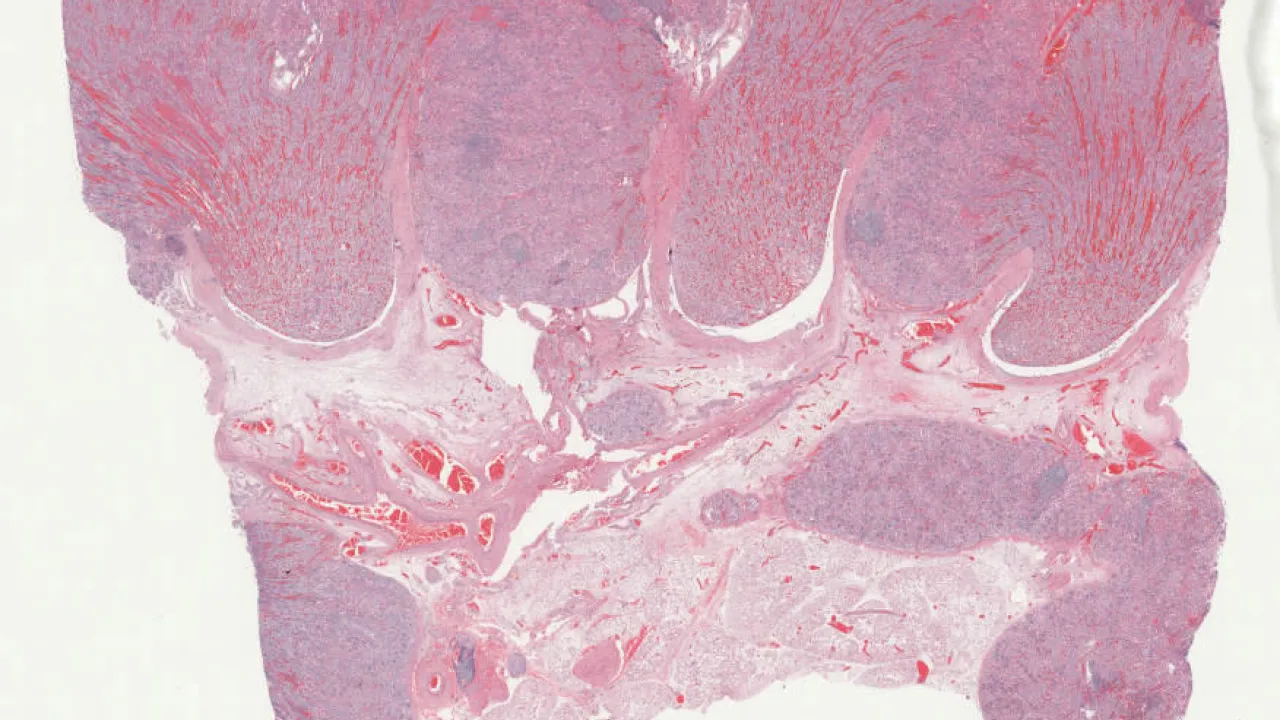

Kidney, Xanthogranulomatous pyelonephritis, PAS stain